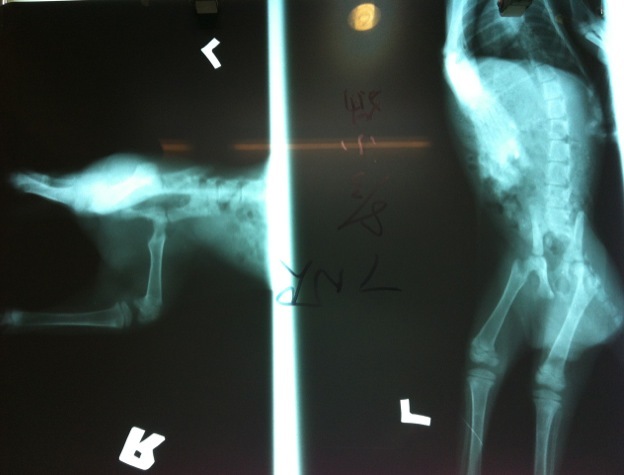

主題: 車禍截尾又爆貓瘟小橘貓,需要您送牠最後一程 申請者姓名: 蔡孟潔 花色: 申請日期: 2012-08-22 16:45:22 申請者部落格: http://www.facebook.com/mengjiec2 申請者臉書網址: http://www.facebook.com/media/set/?set=a.472550629431447.112786.100000295417084&type=1 所在縣市/合作醫院: 花蓮縣/建國動物診所 治療費用: 2150元 需求人數: 10人 已結案 (2013-06-27 13:27:49) 報名人員: Bei Bei Wang(已付款)、Hope Liao(已付款)、Chinia(已付款)、陳阿妹(已付款)、Lorelei Tsai(已付款)、Lorelei Tsai、Lorelei Tsai、小恩、Agatha、amychen(已付款)、julie lee(已付款)、meemee(已付款)、meemee(已付款)、小舟、美珍沈(已付款)、 候補人員: 小舟、 動物病情說明: 8/3 R貓時發現二隻被棄養的小貓(暹邏、橘子),其中一隻橘貓尾巴沒有反應,疑似斷掉,剛醫師說小貓是車禍,診斷後需截掉尾巴,脊椎有斷裂需照x光

因車禍致最後腰椎及尾椎嚴重損傷,貓咪傷口車禍至送院開刀為止醫師判斷已有5-7天,且尾巴(尾根基部組織)整條坏死,但後肢仍可站立(勉強)及排便,經考慮後決定先手術切除坏死尾巴(整條),手術後恢復良好,亦漸漸可走動。